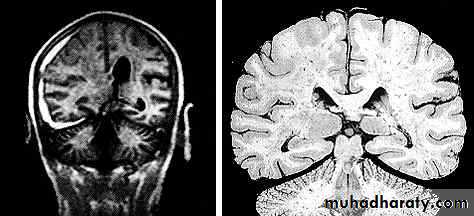

1. Diffuse Axonal Injury

Prolonged post-traumatic state in which there is loss of consciousness from the time of injury that continues beyond 6 hours.Occurs as a result of mechanical shearing at the grey-white matter interface.

This causes disruption and tearing of axons, myelin sheaths and blood capillaries.

Severity can range from mild damage with confusion to coma and even death.